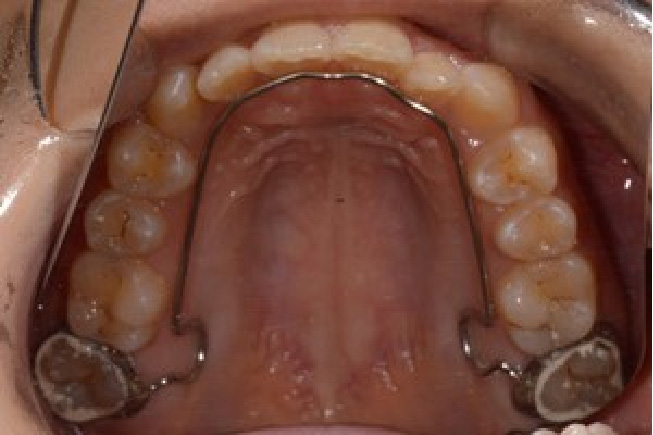

• 予防矯正

歯並びの改善や、筋機能改善(適応年齢3~17歳程度)

歯ならびだけでなく、口の周りや舌の筋肉の機能の改善。正常な成長発育を促す予防的な矯正治療。

【自費診療:プレオルソ:55,000円、交換:11,000円、 床矯正、その他装置 77,000円~】